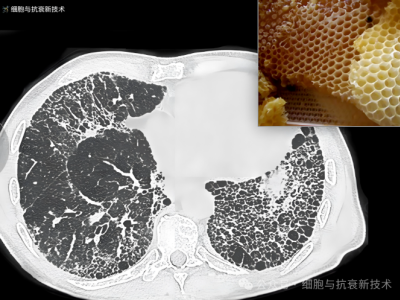

外泌體霧化可治療肺部結(jié)節(jié)及肺纖維化

2019年新冠疫情后,大家對(duì)肺部損傷比較關(guān)注,加之生活工作壓力以及檢測技術(shù)的進(jìn)步,使結(jié)節(jié)成為體檢報(bào)告上出現(xiàn)的高頻詞匯,其中包括肺部結(jié)節(jié),結(jié)節(jié)的出現(xiàn)給部分人群增添了焦慮。外泌體作為先進(jìn)治療藥品,是當(dāng)前生